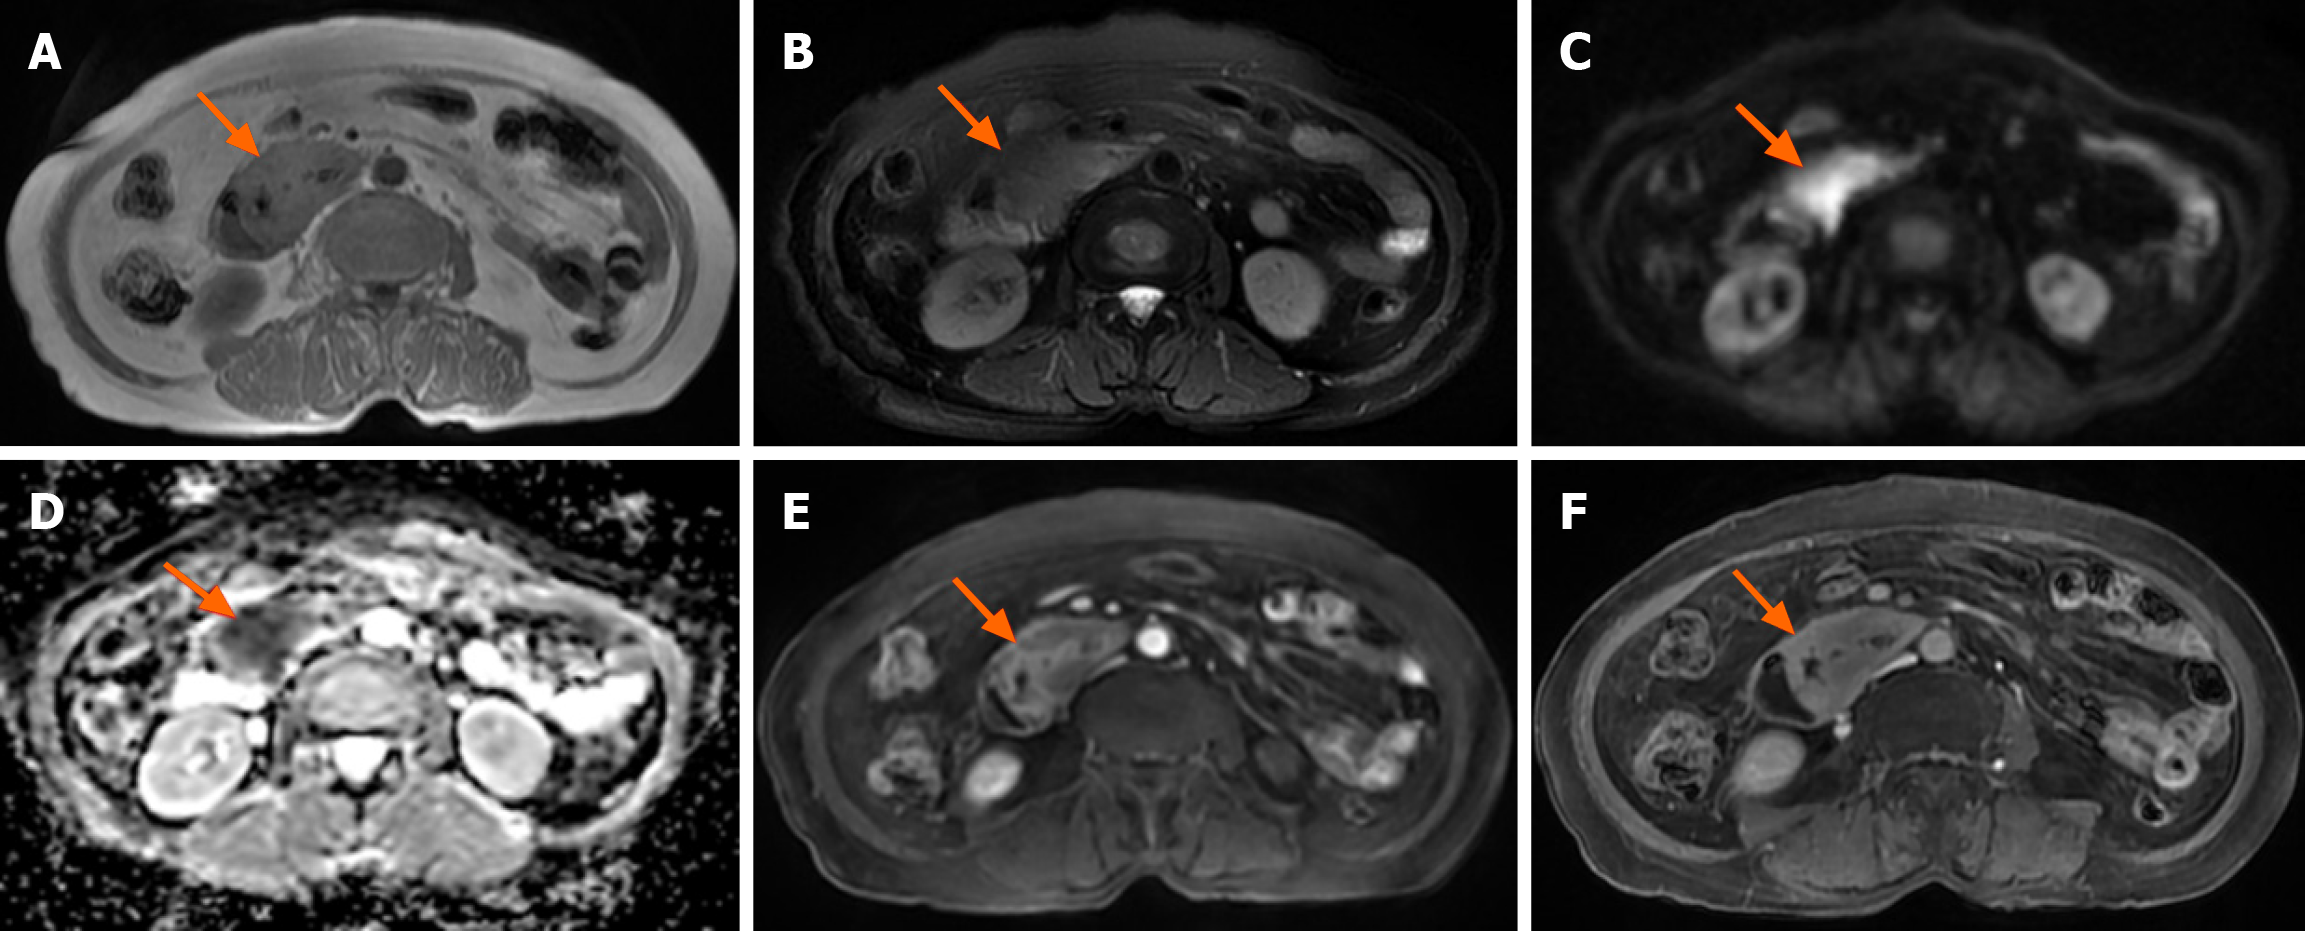

18F-FDG PET/CT revealed multiple segmental thickening in the descending and horizontal segments of the duodenum, jejunum, and ileum. The horizontal segment of the duodenum had the largest lesion, approximately 5 cm × 4 cm in size. The intestinal tract showed aneurysmal dilatation with stenosis and obstruction of the intestinal lumen, and the maximal standardized uptake value (SUVmax) was 9.2 (Figure 1). The SUVmax reflects the uptake of 18F-FDG and the metabolic activity of the lesion. Multiple enlarged lymph nodes were found in the abdominal and pelvic mesentery. The largest lesion was 0.9 cm × 0.7 cm in size, with an SUVmax of 3.1 (Figure 1). A plain MR scan of the upper abdomen revealed that the larger lesion in the horizontal segment of the duodenum presented an iso-signal on T1 weighted imaging (T1WI) and an iso- or hypo-signal on T2WI. It was hyperintense on diffusion-weighted imaging, and the apparent diffusion coefficient was 0.8 × 10-3 mm2/second. Post-contrast MR imaging (MRI) demonstrated delayed and homogeneous enhancement (Figure 2). Gastroduodenoscopy revealed cauliflower-like masses in the duodenal lumen, marked narrowing and obstruction of the intestinal lumen (Figure 3).

Currently, there are few imaging reports on MEITL. The previously reported cases are shown in Table 1. According to previous reports, MEITL can involve the whole intestine, with increased FDG uptake in the lesion and an SUV ranged 3.3 to 10.2[8]. Our patient also presented with multiple lesions in the small intestine, with a SUVmax of 9.2, which is consistent with previous reports in the literature. Intestinal lymphoma typically does not involve organ metastasis. However, in rare instances, MEITL may metastasize to the lung, liver, central nervous system and bone marrow[8-11]. MR examination shows iso- or hypo-signals on T2WI and limited diffusion on diffusion-weighted imaging, which is attributable to the abundance of tumor cells and the diminished concentration of extracellular fluid. On an enhanced scan, MEITL exhibits delayed and homogeneous enhancement, which is similar to the performance in a previous report[8]. These findings suggest that MEITL is generally characterized by the absence of necrosis. A search of the PubMed database found five case reports of MEITL that presented with MRI and/or 18F-FDG PET/CT findings (Table 1)[8-10,12,13].